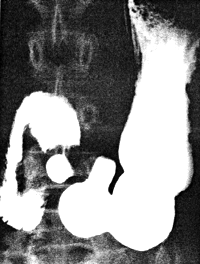

![]() |

| Fig. 13.5. Normal pyloric ring (arrow) in motor quiescent phase. Width of ring on lesser curvature more or less equal to that on greater curvature. Note patent pyloric aperture with diameter of 9 mm, containing barium |

After a variable interval peristaltic contractions commenced in the gastric corpus in all cases. These narrow, annular waves were seen to proceed along the body of the stomach in a caudal direction as far as a point 3.0 to 4.0 cm proximal to the pyloric aperture. At this point each caudally travelling peristaltic wave came to a halt, i.e. it failed to advance any further, and ended in a concentric or cylindrical contraction of the entire distal 3.0 to 4.0 cm of the stomach (Fig. 13.6).

| Fig. 13.6. Point at which peristaltic wave stops (curved arrows). Pyloric aperture (straight arrow). The region between the curved and straight arrows is distal 3-4 cm of stomach. |